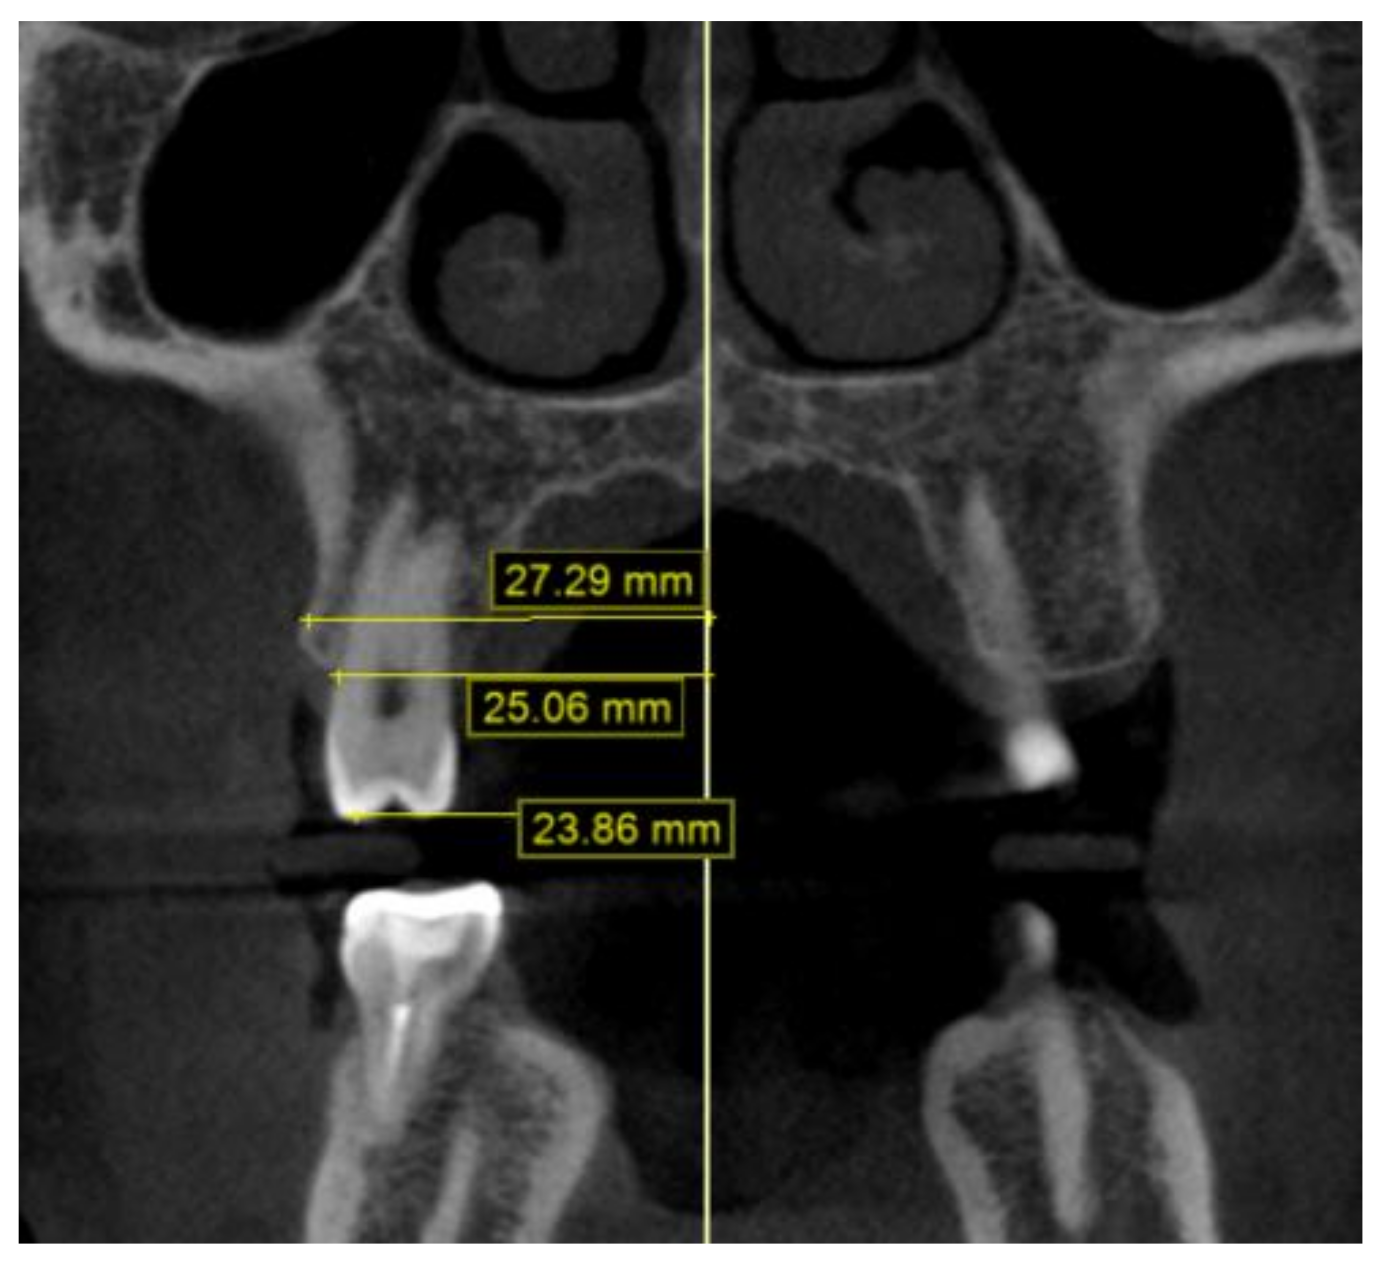

2.2. Methodology of Measurements

4.5. Transverse Measurements on CBCT Scans versus Casts